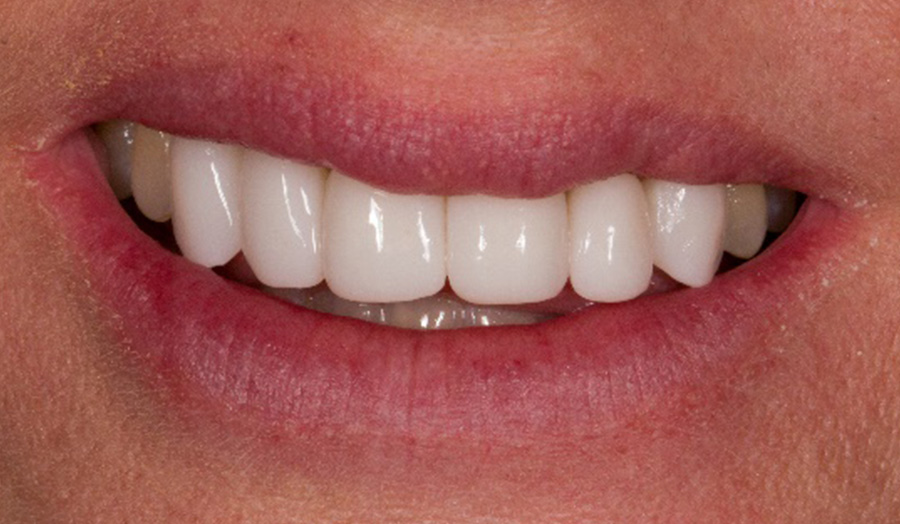

A 47-year-old female presented to my office with concerns about six anterior zirconia crowns recently done at another office. The efficiency and ease of use of the Primeprint Solution allows me to quickly print models on the same day of treatment which enables me to present a preview of treatment to patient before the final production with CEREC Primemill.

Before: Initial oral situation with significant asymmetry of the lips when smiling

After: Final restoration